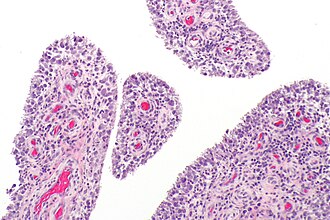

Acute synovitis. H&E stain. | |

| LM | synovium with neutrophils |

Microscopic

Features:

- Synovium with abundant neutrophils.

- No significant number of plasma cells.